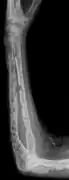

Medical imaging

The diagnostic examination of a person with suspected multiple myeloma typically includes a skeletal survey. This is a series of X-rays of the skull, axial skeleton, and proximal long bones. Myeloma activity sometimes appears as "lytic lesions" (with local disappearance of normal bone due to resorption) or as "punched-out lesions" on the skull X-ray ("raindrop skull"). Lesions may also be sclerotic, which is seen as radiodense.[70] Overall, the radiodensity of myeloma is between −30 and 120 Hounsfield units (HU).[71] Magnetic resonance imaging is more sensitive than simple X-rays in the detection of lytic lesions, and may supersede a skeletal survey, especially when vertebral disease is suspected. Occasionally, a CT scan is performed to measure the size of soft-tissue plasmacytomas. Nuclear Medicine Bone scans are typically not of any additional value in the workup of people with myeloma (no new bone formation; lytic lesions not well visualized on nuclear bone scan).